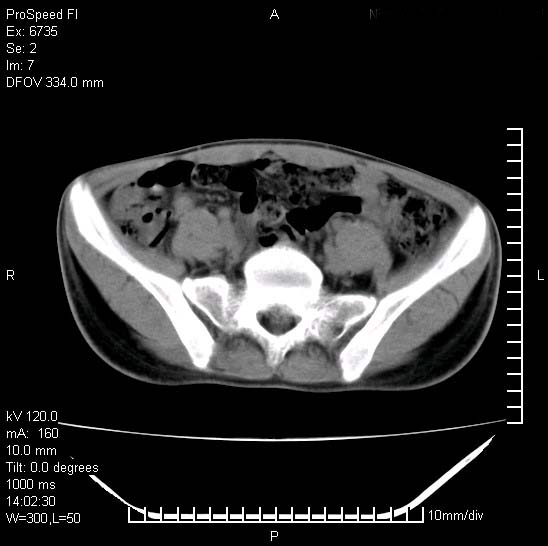

患者自诉胯部疼痛两年余,在当地服用中药,半月前至本院考虑骶髂关节结核,给予抗痨治疗。现发展至右下肢疼痛明显,活动受限,以膝关节处明显,拍膝关节平片无明显异常。

两侧骶骼关节改变,考虑强直性脊炎

左侧骶髂关节面限局性骨破坏,边缘硬化关节腔见钙化物;不出外tb

右侧骶髂关节也有类似改变,只是较左侧轻,首先考虑强直性脊柱炎,不除外结核,建议作hla-b27检查。

典型强脊炎改变,髋关节亦有累及

符合强直性脊柱炎表现。